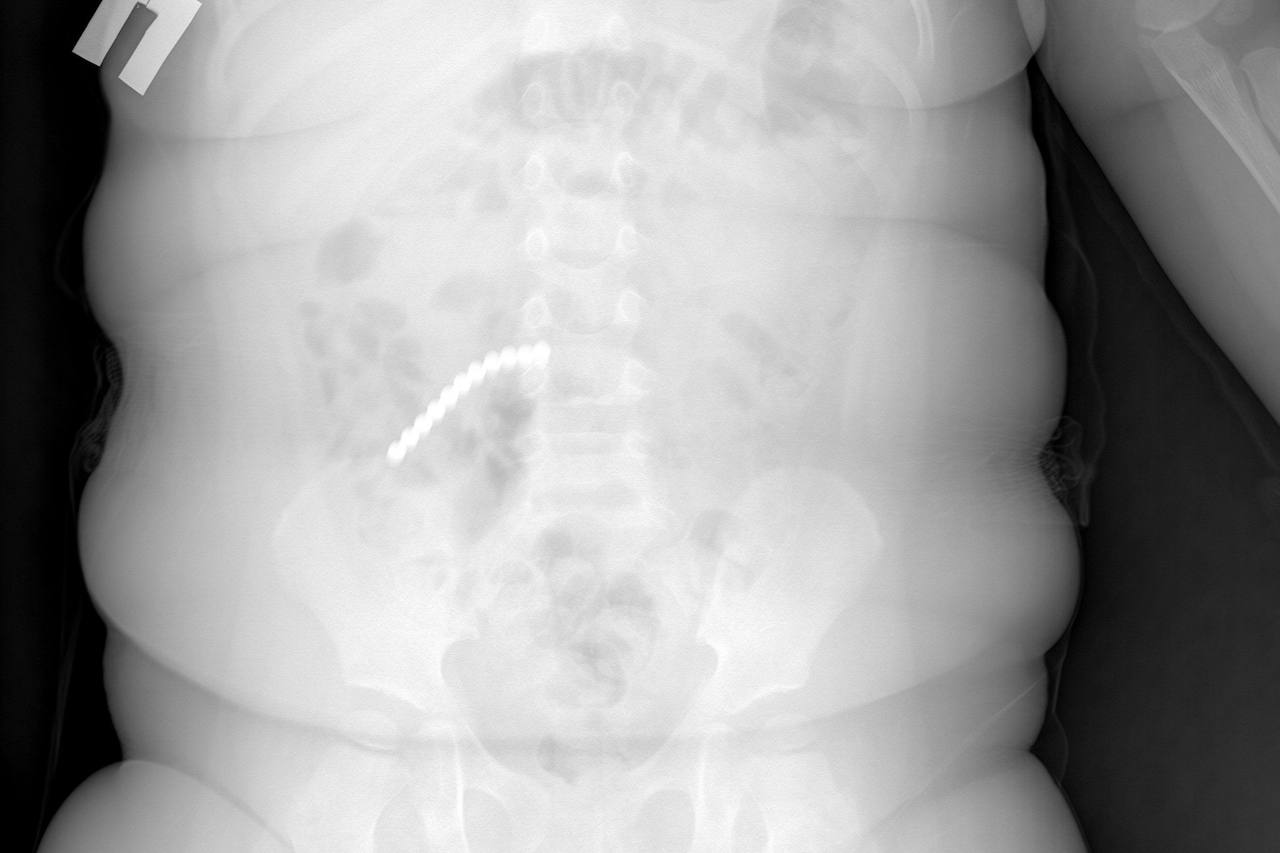

Двухлетний ребенок поступил в больницу с сильной рвотой и вялостью. Сначала родители думали - отравление или вирус. Но когда сделали рентген, врачи увидели страшное. Почти весь кишечник был усеян мелкими шариками. Как выяснилось, пациент проглотил 20 шариков от магнитного конструктора - неокуба.

Девять деталей врачам удалось достать через эндоскоп. Но основная проблема была впереди. Остальные магниты разошлись по кишечнику и начали притягиваться друг к другу через стенки кишок. Из-за этого петли тонкой, слепой и сигмовидной кишки буквально слиплись между собой. Началось воспаление, образовались дырки - перфорации.

- Магниты спрессовали кишки, возникли свищи. Часть шариков даже попала в аппендикс. Пришлось удалять и его тоже, - рассказал хирург Вячеслав Данчинов.